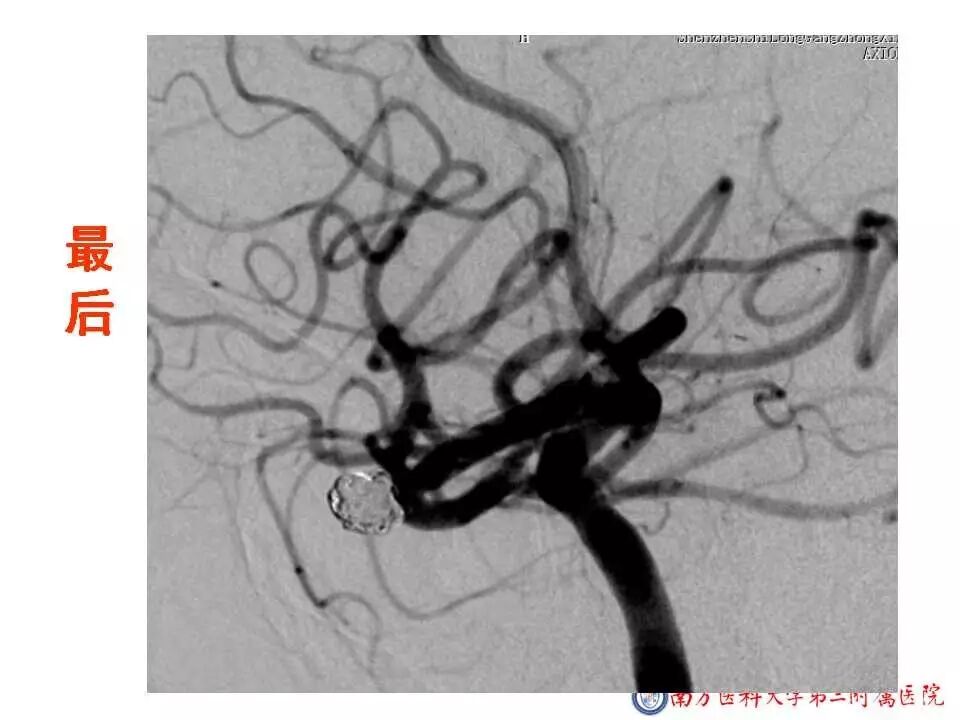

今天为大家分享的是“强生医疗CNV-神经介入专栏”第二十五期,由南方医科大学第三附属医院神经外科主任黄理金教授带来的“Enterprise支架辅助栓塞动脉瘤的优势”精彩讲课视频及PPT,欢迎观看。文章仅代表作者个人观点,如有不同见解,欢迎同道斧正!